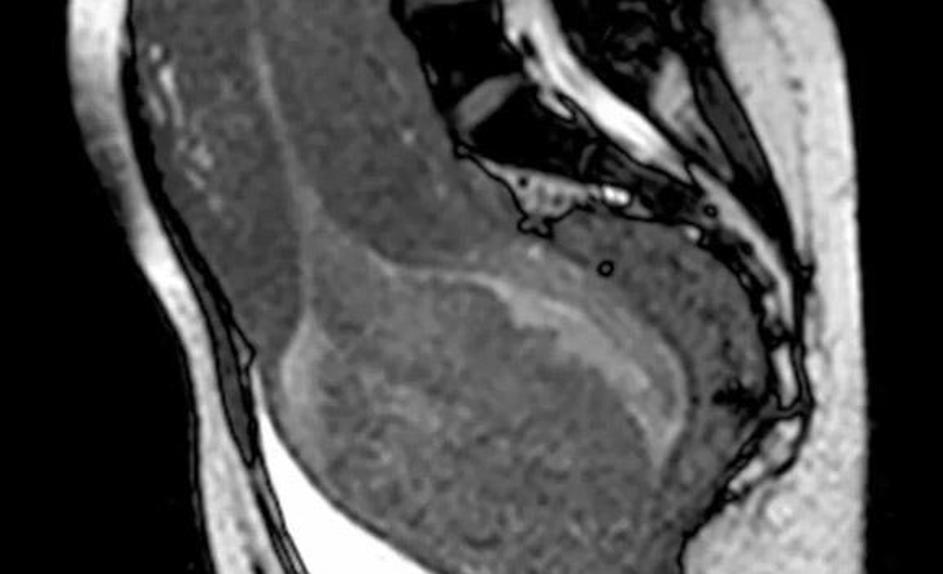

porod, snemanje, magnetna resonanca Sprednji pogled glave otroka v medeničnem vratu. Žurnal24 porod, snemanje, magnetna resonanca